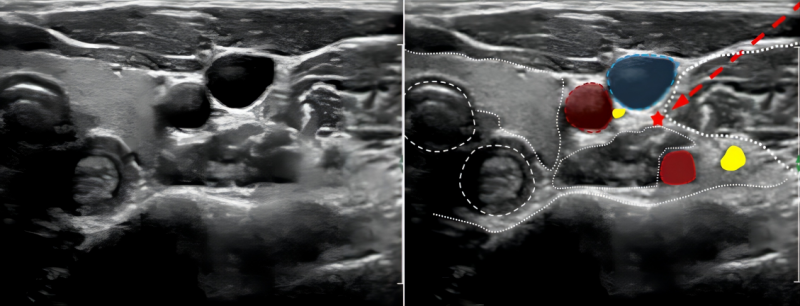

云中二院讯(通讯员 林永生)2024年1月18日,医院康复医学科成功完成首例超声引导下“星状神经节阻滞术”,有效解决该名患者中风后肩手综合征及相关并发症。当天下午及次日,多位患者相继完成肌骨超声治疗,均反馈效果显著。

星状神经节阻滞(SGB)是将局部麻醉药物注入SG周围及附近组织,包括颈交感干、颈交感神经节、节前与节后神经及其支配范围的区域,从而阻滞支配头、面、颈、肩胛、上肢、前胸及后背等部位的交感神经,以调节交感神经系统张力,最终达到调节人体的自主神经系统、循环系统、内分泌系统、免疫系统使其保持动态平衡的作用,用于治疗多种疼痛及非疼痛类疾病。